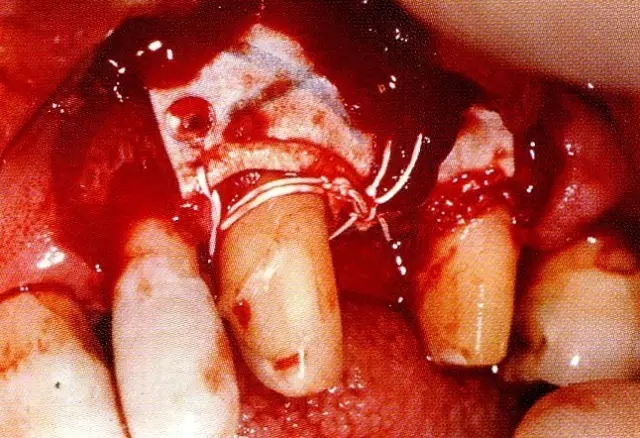

▲圖7-4  術(shù)后1年2個(gè)月再翻開看的情況。與圖7-1的骨缺損狀態(tài)相比可知形成了臨床性骨再生。